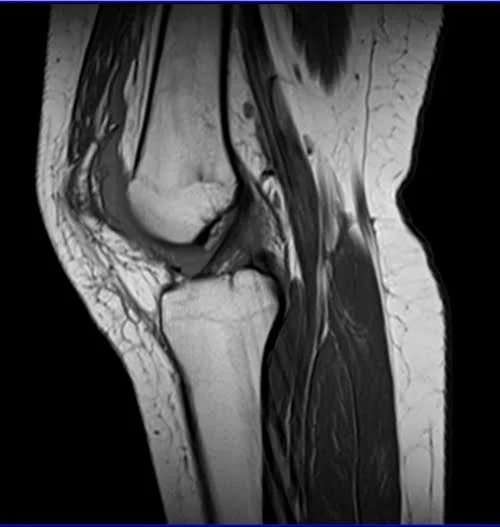

MRI knee sagittal t1 2 - MRI